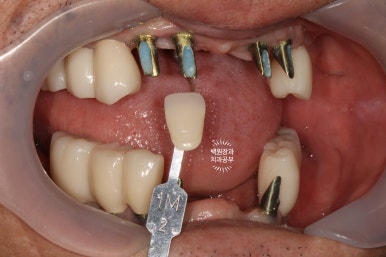

임시보철물을 제거하고 내부의 기둥이 보이는 모습입니다.

환자분과 함께 원하시는 치아 색상을 정해서 기공소에 전달하면, 이제 드디어 최종 보철물이 제작되어 옵니다.

옛날부터 임플란트 틀니용으로 사용하시던 임플란트 3개는 임플란트 주위염이 조금 있어 약~간 쇠기둥 색깔이 보인다는 단점이 있긴 하지만, 다른 임플란트들은 꽤나 예쁘게 제작이 되었네요.